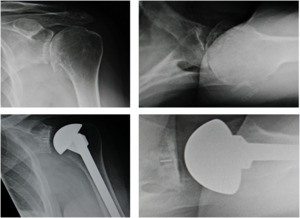

_and_postoperative_(bottom_images)_x-ray_images_of_a_patient_with.png)

This short-term clinical study is a retrospective review of seven consecutive patients with advanced arthritis and glenoid bone loss. Since standard implants were contraindicated because of the severe glenoid vault destruction, these patients were all treated with custom inset glenoid implants. At the minimum 3 year clinical follow up, analysis was performed using the prospectively collected clinical data, XRs, and outcome study data. At the mean 4.3 year follow up, ASES scores improved an average of 68 points (pre-op 26 to final post-op 94). Range of motion improved with statistical significance in all directions. VAS pain scores improved from a mean of 6.9 to 0.1. There were no loose or “at risk” glenoids according to independent radiographic analysis. There were no surgical complications and no revision surgeries (Gunther and Lynch 2012).

This article evaluates long-term results of inset glenoid fixation for severely deficient bone. A consecutive series of 24 patients were evaluated with final outcome scores, VAS pain scores, radiographs, and clinical measures. Most of the patients (21/ 24) were still alive and available for final follow up. Full clinical follow-ups and XRs were performed on 14 patients. Telephone interviews were performed for 7 patients who could not travel to the clinic. This enabled documentation of VAS pain scores, ASES outcome scores, and any history of any complications or revision surgery. Minimum follow-up was 6 years. At the mean follow-up of 8.7 years, there was statistically significant improvement (p<.0001) in visual analog pain scores, ASES outcome scores, and range of motion. Final mean pain score was 0.1 (scale 0-10), and final mean ASES score was 95 (scale 0-100). There were no loose glenoid implants. There were no surgical complications. There was no revision surgery. This publication documented the long-term success of inset glenoid fixation in the most severe glenoid bone deficiency cases in which standard glenoid implants were contraindicated (Gunther and Tran 2019).